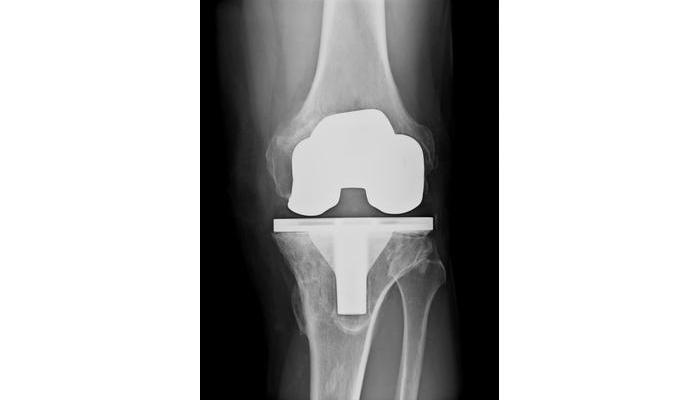

Case Study: Total Knee Replacement Patient with Wound Dehiscence Due to Lymphedema

Patient L entered our facility from an acute care hospital. She had already failed discharge home and arrived with a diagnosis of incision and drainage of her infected knee replacement with heavy wound drainage. She required more than one dressing change per day (even with wicking ultra-absorbent dressings). Her topical dressing was changed to a post-op negative pressure wound therapy (NPWT) dressing at 125mmHg continuous. The dressing was applied in a partially flexed position to allow range of motion (ROM) exercises. Output required changing the 300ml canister BID. Her comorbid diagnosis of chronic lymphedema was obviously slowing the healing of her surgical incision such that even the NPWT pump could not keep up with it. Her physicians cleared her for Manual Lymphatic Drainage (MLD) and multilayer compression bandaging when an ABI showed adequate arterial circulation.